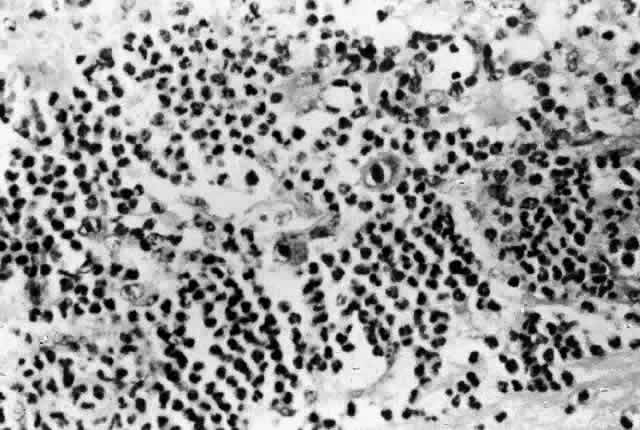

Histologic studies of AIDS-related CMV retinopathy demonstrate the tissue necrosis and cytomegalic cells characteristic of all CMV infections (Fig. 1).9,17 Electron-microscopic and immunochemical studies have identified CMV viral particles and antigen in a patchy distribution throughout all layers of the retina and occasionally in contiguous retinal pigment epithelial cells.9 Viral antigens are only rarely identified in the choroid.9,18 Viral antigen in the choroid has been found in association with vessels and is not always adjacent to areas of retinopathy, suggesting that the virus reaches the choroid through independent hematogenous spread rather than by extension of infection from the retina.

Among cases of AIDS examined at autopsy, 22% to 50% of those with CMV retinopathy have neutrophilic infiltrates in retinal tissue.9,19 This finding is atypical when compared with CMV retinopathy in non-AIDS patients, in which only a sparse lymphocytic infiltrate is observed. The difference has been attributed to intact granulocyte function and chemotaxis in patients with AIDS, in contrast to infants, organ transplant recipients, and patients with malignancies who can have more severe quantitative or qualitative granulocyte dysfunction.9 It has been noted that patients on immunosuppressive drugs can develop marked inflammatory reactions to CMV retinopathy when such drugs are withdrawn.14 Acute inflammatory cells may extend into the adjacent choroid despite the absence of identifiable viral antigens.9 The vitreous usually remains remarkably free of inflammatory material, despite the presence of virus in the vitreous cavity.20